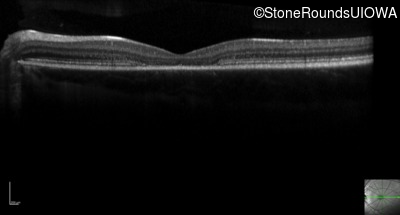

Optical Coherence Tomography - Left - 20/80

Exemplar / OCT Stack

OCT Stack